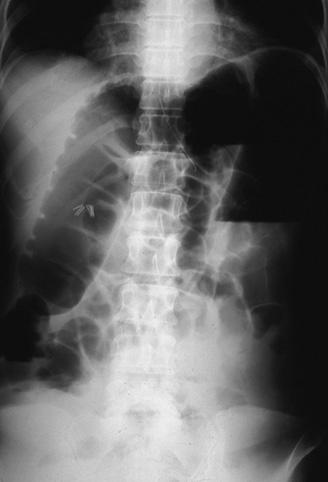

疾病(病理主体)的分类良性非上皮性肿瘤/脂肪瘤

部位(按器官分)大肠/降结肠

检查方法X线

肿瘤最大直径35~40